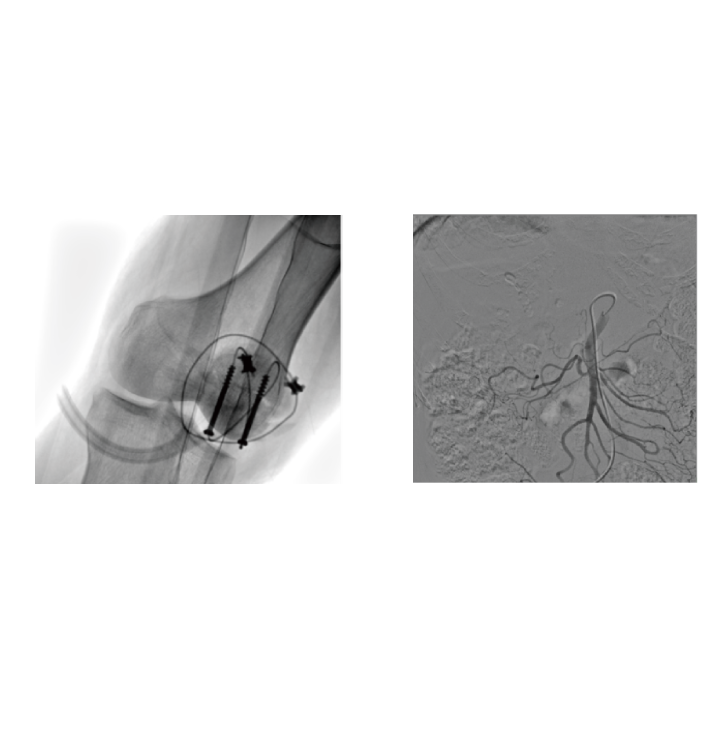

- 3. Abrangente Cobertura de Cenários Cirúrgicos e Intervencionistas

-Da ortopedia e cirurgia traumática à intervenção periférica, apoia totalmente a cirurgia aberta e cenários de intervenção minimamente invasivos. Um dispositivo atende a diversas necessidades e ajuda os hospitais a otimizar a alocação de recursos.